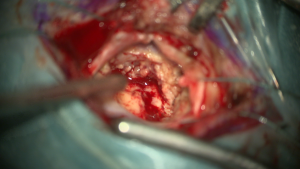

Zur besseren Darstellung setzt Prof. Feigl bei höhergradigen hirneigenen Tumoren immer die 5-ALA Fluoreszenz ein Abbildung 1 und 2: Im ersten Bild ist die Hirnoberfläche unter dem Mikroskop mit Weißlicht und im zweiten mit Blaulicht zu sehen. Unter dem Blaulicht fluoresziert (= leuchtet) der Tumor und kann so bei der Entfernung eindeutig von gesundem Hirngewebe abgegrenzt werden.